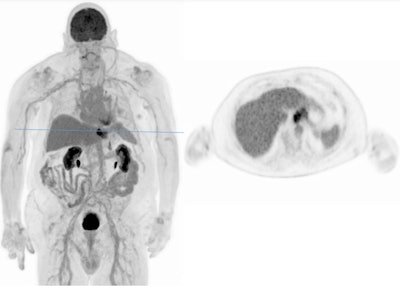

PET in a patient with lymph node metastatic disease from malignant melanoma. Tiny hypermetabolic lymph nodes detected in a two-minute scan (Biograph Vision Quadra PET/CT from Siemens, 120 min. p.i., 220 MBq FDG). All images courtesy of Prof. Dr. Axel Rominger."You don't need to shuffle patients back and forth when acquiring dynamic 4D data, and drug discovery is also very much supported by these new devices," he said, adding that PET acquisition can be significantly shortened with the new scanners, while image quality remains outstanding.

In a patient with malignant melanoma, Rominger and his colleagues artificially reduced the acquisition time down to 30 seconds and managed to image tiny lymph nodes. "We don't miss any small hypermetabolic metastases. In such short scans, image quality becomes worse and noise is increasing, but you could theoretically work with these scans."